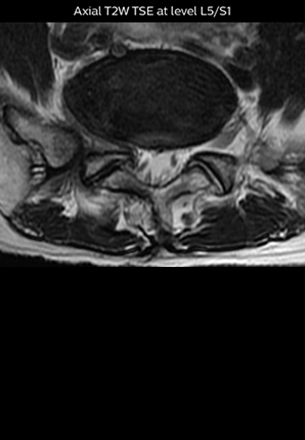

At Northern Fukushima Medical Center in Japan, excellent MRI visualization of nerves helps support confident diagnoses and informs surgical treatment decisions for patients with lower limb symptoms. MRI technologist Tanji and orthopedic surgeon Dr. Yabuki share how direct nerve visualization with the 3D NerveVIEW method adds information when diagnosing atypical herniations. The additional insights changed their way of working and benefit their patient care, as illustrated by some clinical examples.

“In patients with lower extremity neurological symptoms, NerveVIEW helps us to determine the disease matching the patient’s symptoms by directly visualizing the nerves. We use the sequence mainly, when there is suspicion of intraforaminal stenosis, extraforaminal stenosis or lateral disc herniation, which is often based on routine T2- and T1-weighted images. Additionally, the excellent depiction of the course of nerves makes NerveVIEW a good navigator when applying treatment such as block therapy or surgery.”

“Although symptoms of typical disc herniation and atypical hernia are very similar, the actual site of herniation is different. It is therefore important to characterize the nerve’s condition both inside and outside of the intervertebral foramina. “Conversely, if we see no abnormality in NerveVIEW, we can assume at least that there is no severe condition that requires surgery. Like this, it can help us avoid unnecessary surgery. NerveVIEW can have a tremendous impact in this way.”

“NerveVIEW is really useful for those cases where a nerve disorder is strongly suspected based on the clinical examination but our regular MRI images do not show any findings. These atypical herniations and spinal canal stenosis, occurring in 5% to 15% of the total lumbar herniation/stenosis cases are our main target when using NerveVIEW,” says Dr. Yabuki.